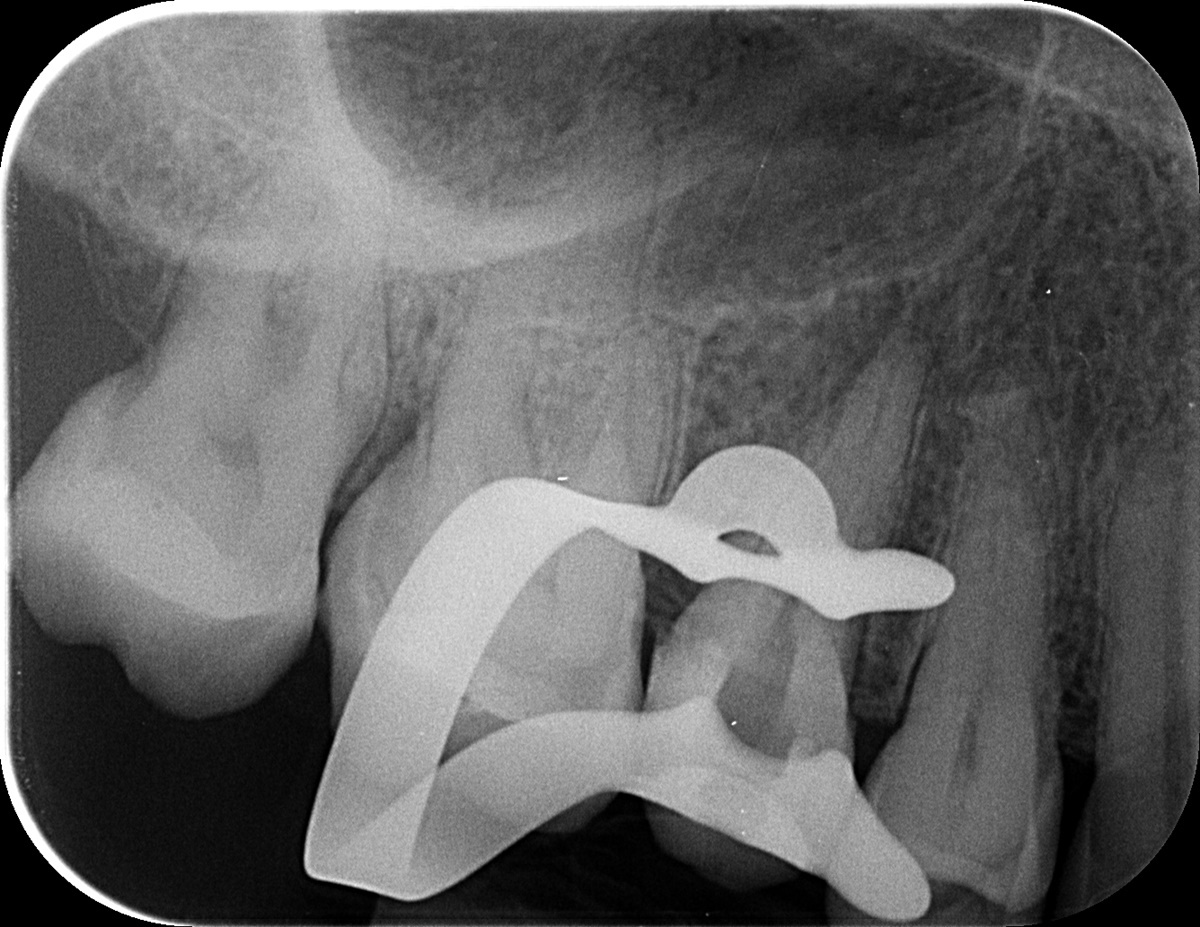

A következő alkalommal alaposan átfertőtlenítettük a csatornákat. Itt már láttuk is, hogy tényleg közös utolsó szakasszal rendelkeznek. Protokoll szerint ismét röntgenfelvétel következett, mellyel ellenőriztük a kiválasztott későbbi gyökértömő pálcika méretét.

mikroszkópos gyökérkezeléssel megmentett fog: a bent rekedt fragmentumok eltávolítása 4